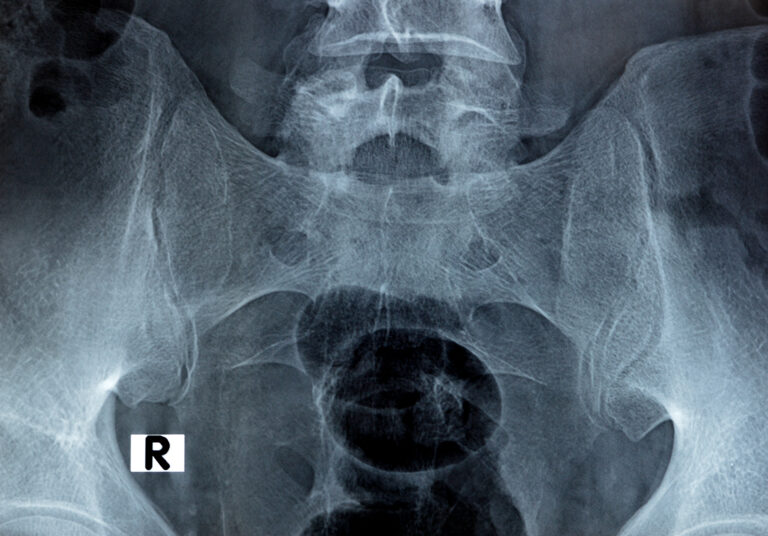

Mal di schiena

Il dolore lombare è una condizione molto frequente. Può avere diverse cause, come problemi muscolari, articolari o discali, e spesso limita le attività quotidiane.